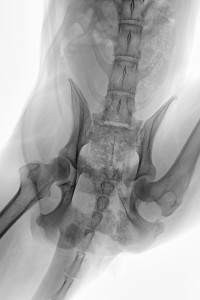

Die letzte RÖ-Kontrolle habe ich am 03. Feb. gemacht und da die Kallusbildung bis dahin weitestgehend abgeschlossen war und der Orthopäde uns grünes Licht gegeben hatte, habe ich Ihr Therapiegerät daher ausschleichend benutzt, d.h. etwa 3 Mal pro Woche für 15 Min.